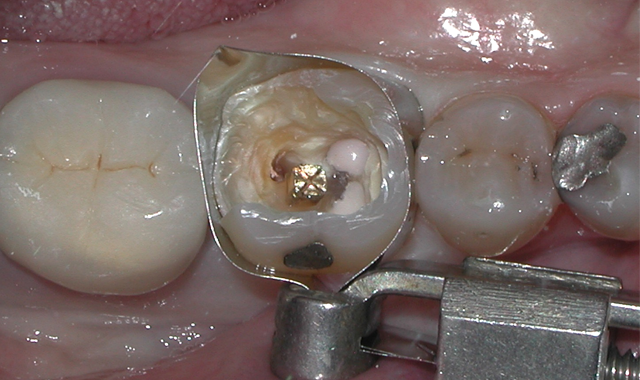

The chamber was then filled using CompCore™ AF (Premier Dental). CompCore AF is a dual-cured, fluoride-releasing, radiopaque composite core buildup indicated for vital and nonvital teeth (Figs. 3-4).

Fig. 4 Fig. 5